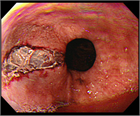

診断

1. 問診では、排出された血液の性状(新鮮血、コーヒー残渣様吐物、タール便、粘血便など)、出血量、持続期間、随伴症状を確認し、喀血との鑑別を行う。

1. 黒色便やBUN/クレアチニン比の上昇は上部消化管出血を疑う重要な所見である。